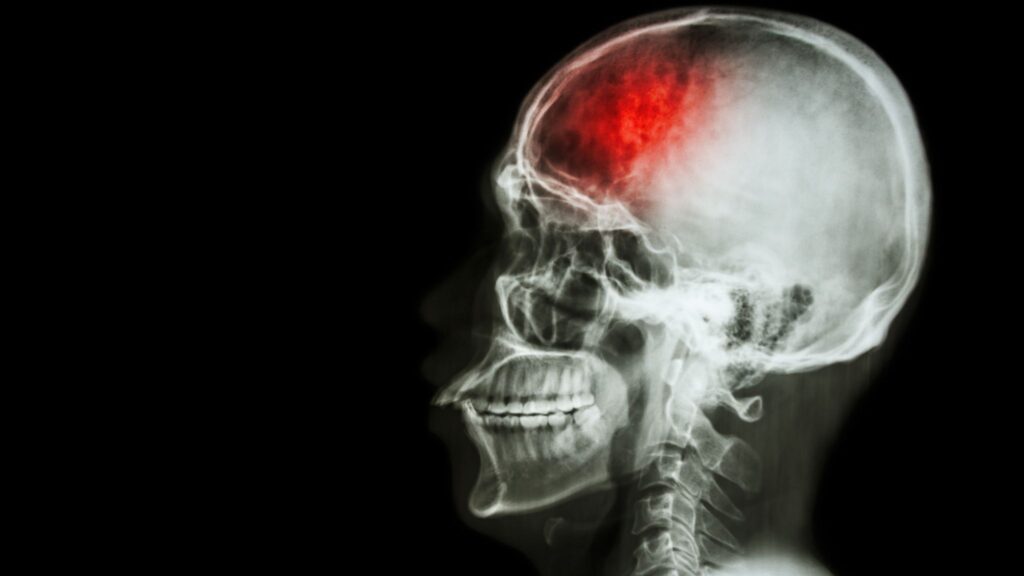

O AVC ocorre quando um vaso sanguíneo que leva sangue ao cérebro se rompe ou entope, interrompendo a circulação em uma parte do órgão. Essa falha impede que as células cerebrais recebam oxigênio, provocando a morte neural e, muitas vezes, sequelas irreversíveis.